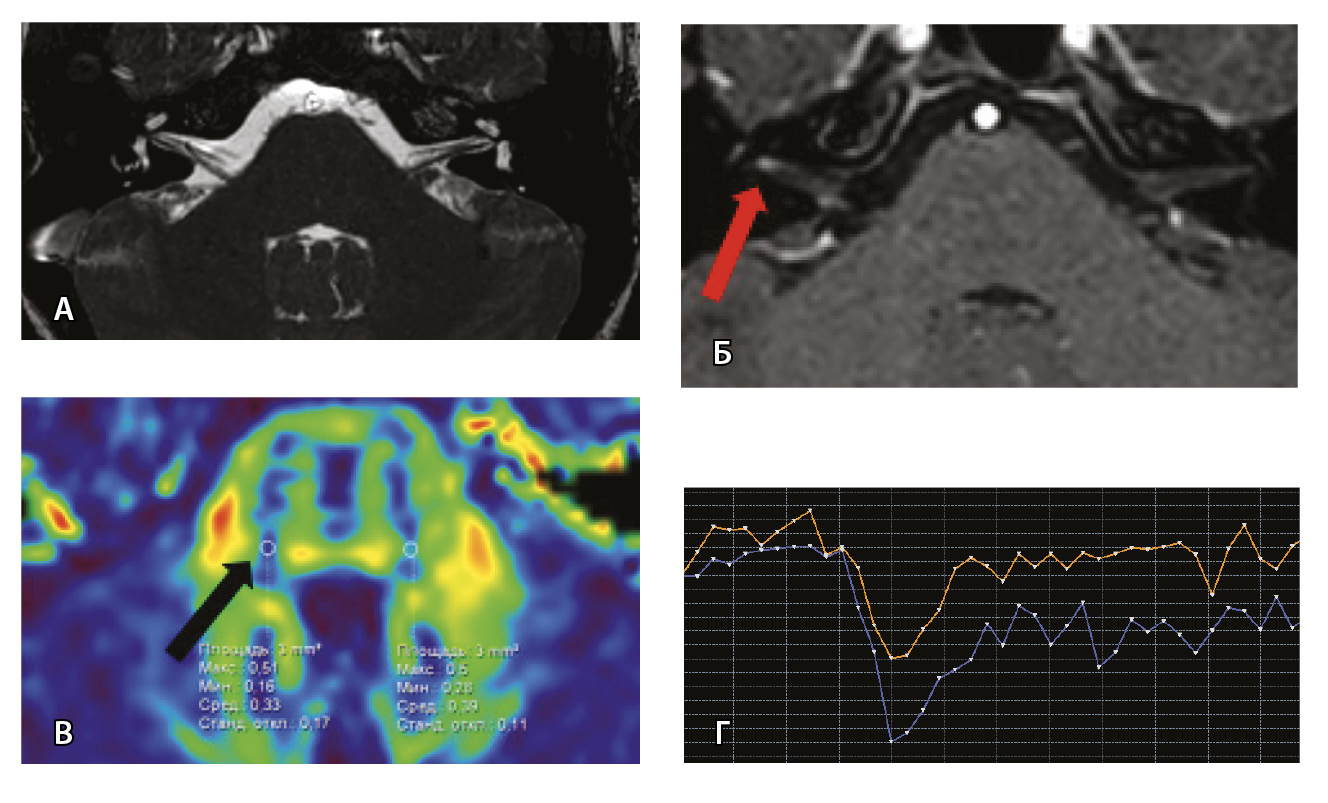

Рис. 3. Пациент Г. Магнитно-резонансная томография (МРТ) головного мозга: А – прицельная T2-SSFP на область мосто-мозжечкового угла; Б – Т1-взвешенное изображение с контрастным усилением; В – диффузионно-тензорная МРТ (фракционная анизотропия); Г – Т2*-перфузия (здесь и далее графики перфузии отражают зависимость повышения интенсивности МР-сигнала, то есть накопления контрастного вещества (вертикальная ось) от времени (горизонтальная ось), тем самым иллюстрируя основные показатели перфузии – relCBV, TTP, MTT). На изображениях T2-SSFP патологические изменения на уровне прохождения лицевых нервов во внутренних слуховых проходах (А), повышенное накопление вещества корешками лицевых нервов (Б) не определяются. Показатели фракционной анизотропии (В) и Т2*-перфузии (Г) на уровне моторных ядер лицевых нервов симметричны

Рис. 6. Пациентка З. Магнитно-резонансная томография (МРТ) головного мозга: А – прицельная T2-SSFP на область мосто-мозжечкового угла; Б – Т1-взвешенное изображение с контрастным усилением; В – диффузионно-тензорная МРТ (фракционная анизотропия, ФА); Г – Т2*-перфузия. На изображении T2-SSFP патологические изменения на уровне прохождения лицевых нервов во внутренних слуховых проходах не определяются (А). При контрастировании отмечается накопление контрастного вещества правым лицевым нервом во внутреннем слуховом проходе (Б, красная стрелка). На уровне моторных ядер лицевого нерва в заднем отделе варолиевого моста на изображениях ФА на стороне поражения отмечается минимальное уменьшение показателя ФА до 0,33 (В, черная стрелка) и признаки гипоперфузии справа (Г, оранжевый график) по сравнению с контралатеральной стороной (Г, синий график). Данный пример демонстрирует типичные изменения при мультипараметрической МРТ у пациента с параличом Белла